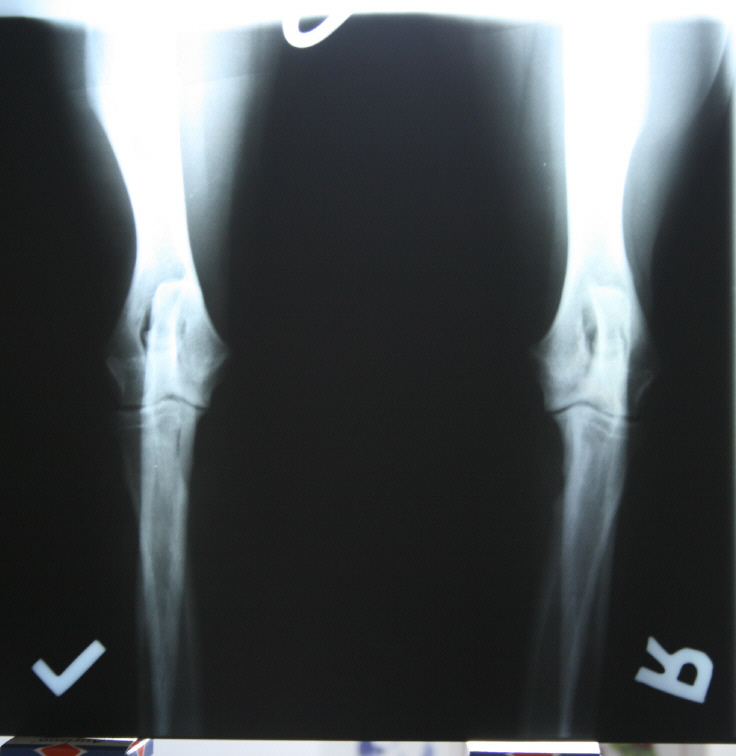

Allys linker Ellbogen gebeugt Allys rechter Ellbogen gebeugt